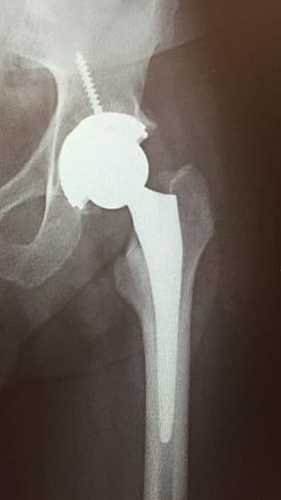

Fiz cirurgia em 2019 para colocação de uma prótese na perna esquerda, conforme foto anexada para que vocês possam ver, no momento preciso colocar a prótese da outra perna.